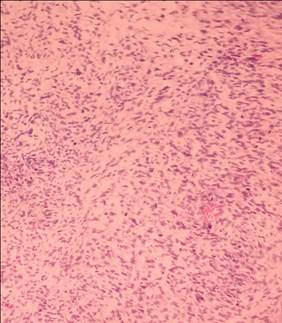

En el estudio histológico solo se observó un estroma hipercelular con marcada atipia nuclear (Figura 3), mitosis, el tumor mostró solo estroma sarcomatoso con elementos epiteliales, ductos mamarios (Figura 4). Diagnóstico: tumor filoide gigante maligno.